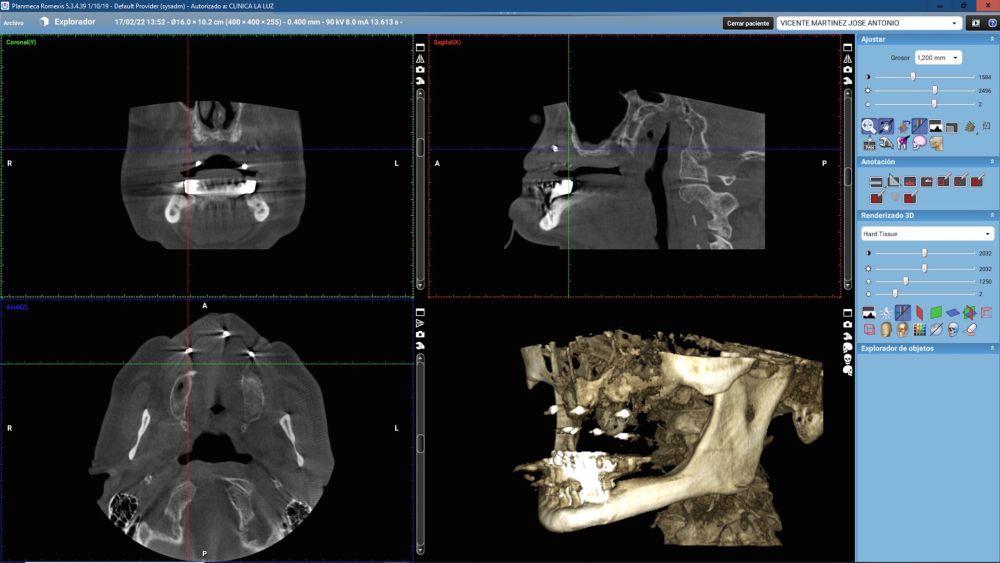

For this purpose, intraoral photographs were made and the complete prosthesis of the patient was used for the different planning tests. First, the double scanning technique was used, adding different radiopaque markers with gutta percha in the prosthesis10 (Figure 3). Then, the scanning was obtained with a conical beam computerized tomography (CBCT), (Planmeca ProMax 3D, Helsinki, Finland), both the prosthesis and the patient with his prosthesis stabilized with a silicone bite registration (Figure 4). In addition, an intraoral scan of the patient’s prosthesis was performed. From this, a personalized structure was designed subperiosteal sintered in Titanium (Ti-6-4) (Custom 3D®) with 6 Multi-Unit® type connections (Branemark, Nobel Biocare) and fixed with osteosynthesis screws in the higher density and volume areas of the malar bone and upper jaw (Figure 5 and 6). At the same time, with the STL digital test of the planning of the mesh, and with the scanning of our complete prosthesis, the laboratory technician made an implantosupported rehabilitation milled in polymethylmethacrylate (PMMA) with Multi-Unit® type titanium interfaces for immediate loading (figures 7 and 8).